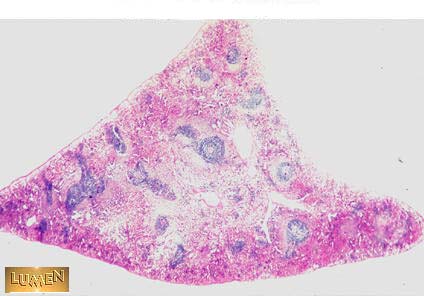

What organ is this?

Spleen